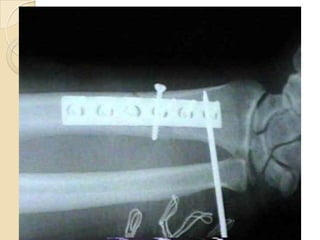

 RAIO-X : deve incluir sempre a articulação do

cotovelo e do punho